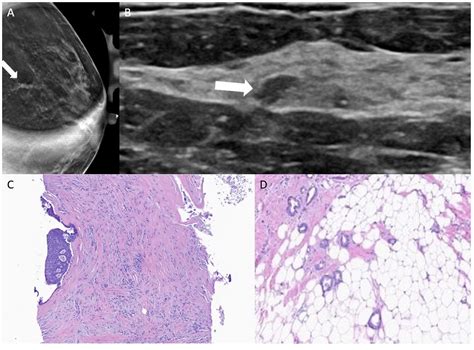

• Mammogram findings: ADH often appears as suspicious microcalcifications (tiny calcium deposits) on a mammogram.

• Incidental discovery: It is frequently found during a breast biopsy performed for another, unrelated reason, such as a breast lump or imaging abnormality.

If a needle biopsy reveals Atypical Ductal Hyperplasia, your doctor will likely recommend an excisional biopsy (often called a surgical biopsy). This is a standard procedure because a needle biopsy only takes a tiny sample of the tissue. Sometimes, the initial biopsy may have missed a larger area of cancer or higher-grade atypical cells located elsewhere within the same lesion.

During an excisional biopsy, the surgeon removes the entire area of concern along with a margin of healthy tissue. This allows the pathologist to examine the entire lesion to confirm the diagnosis and ensure no invasive cancer is hidden nearby.